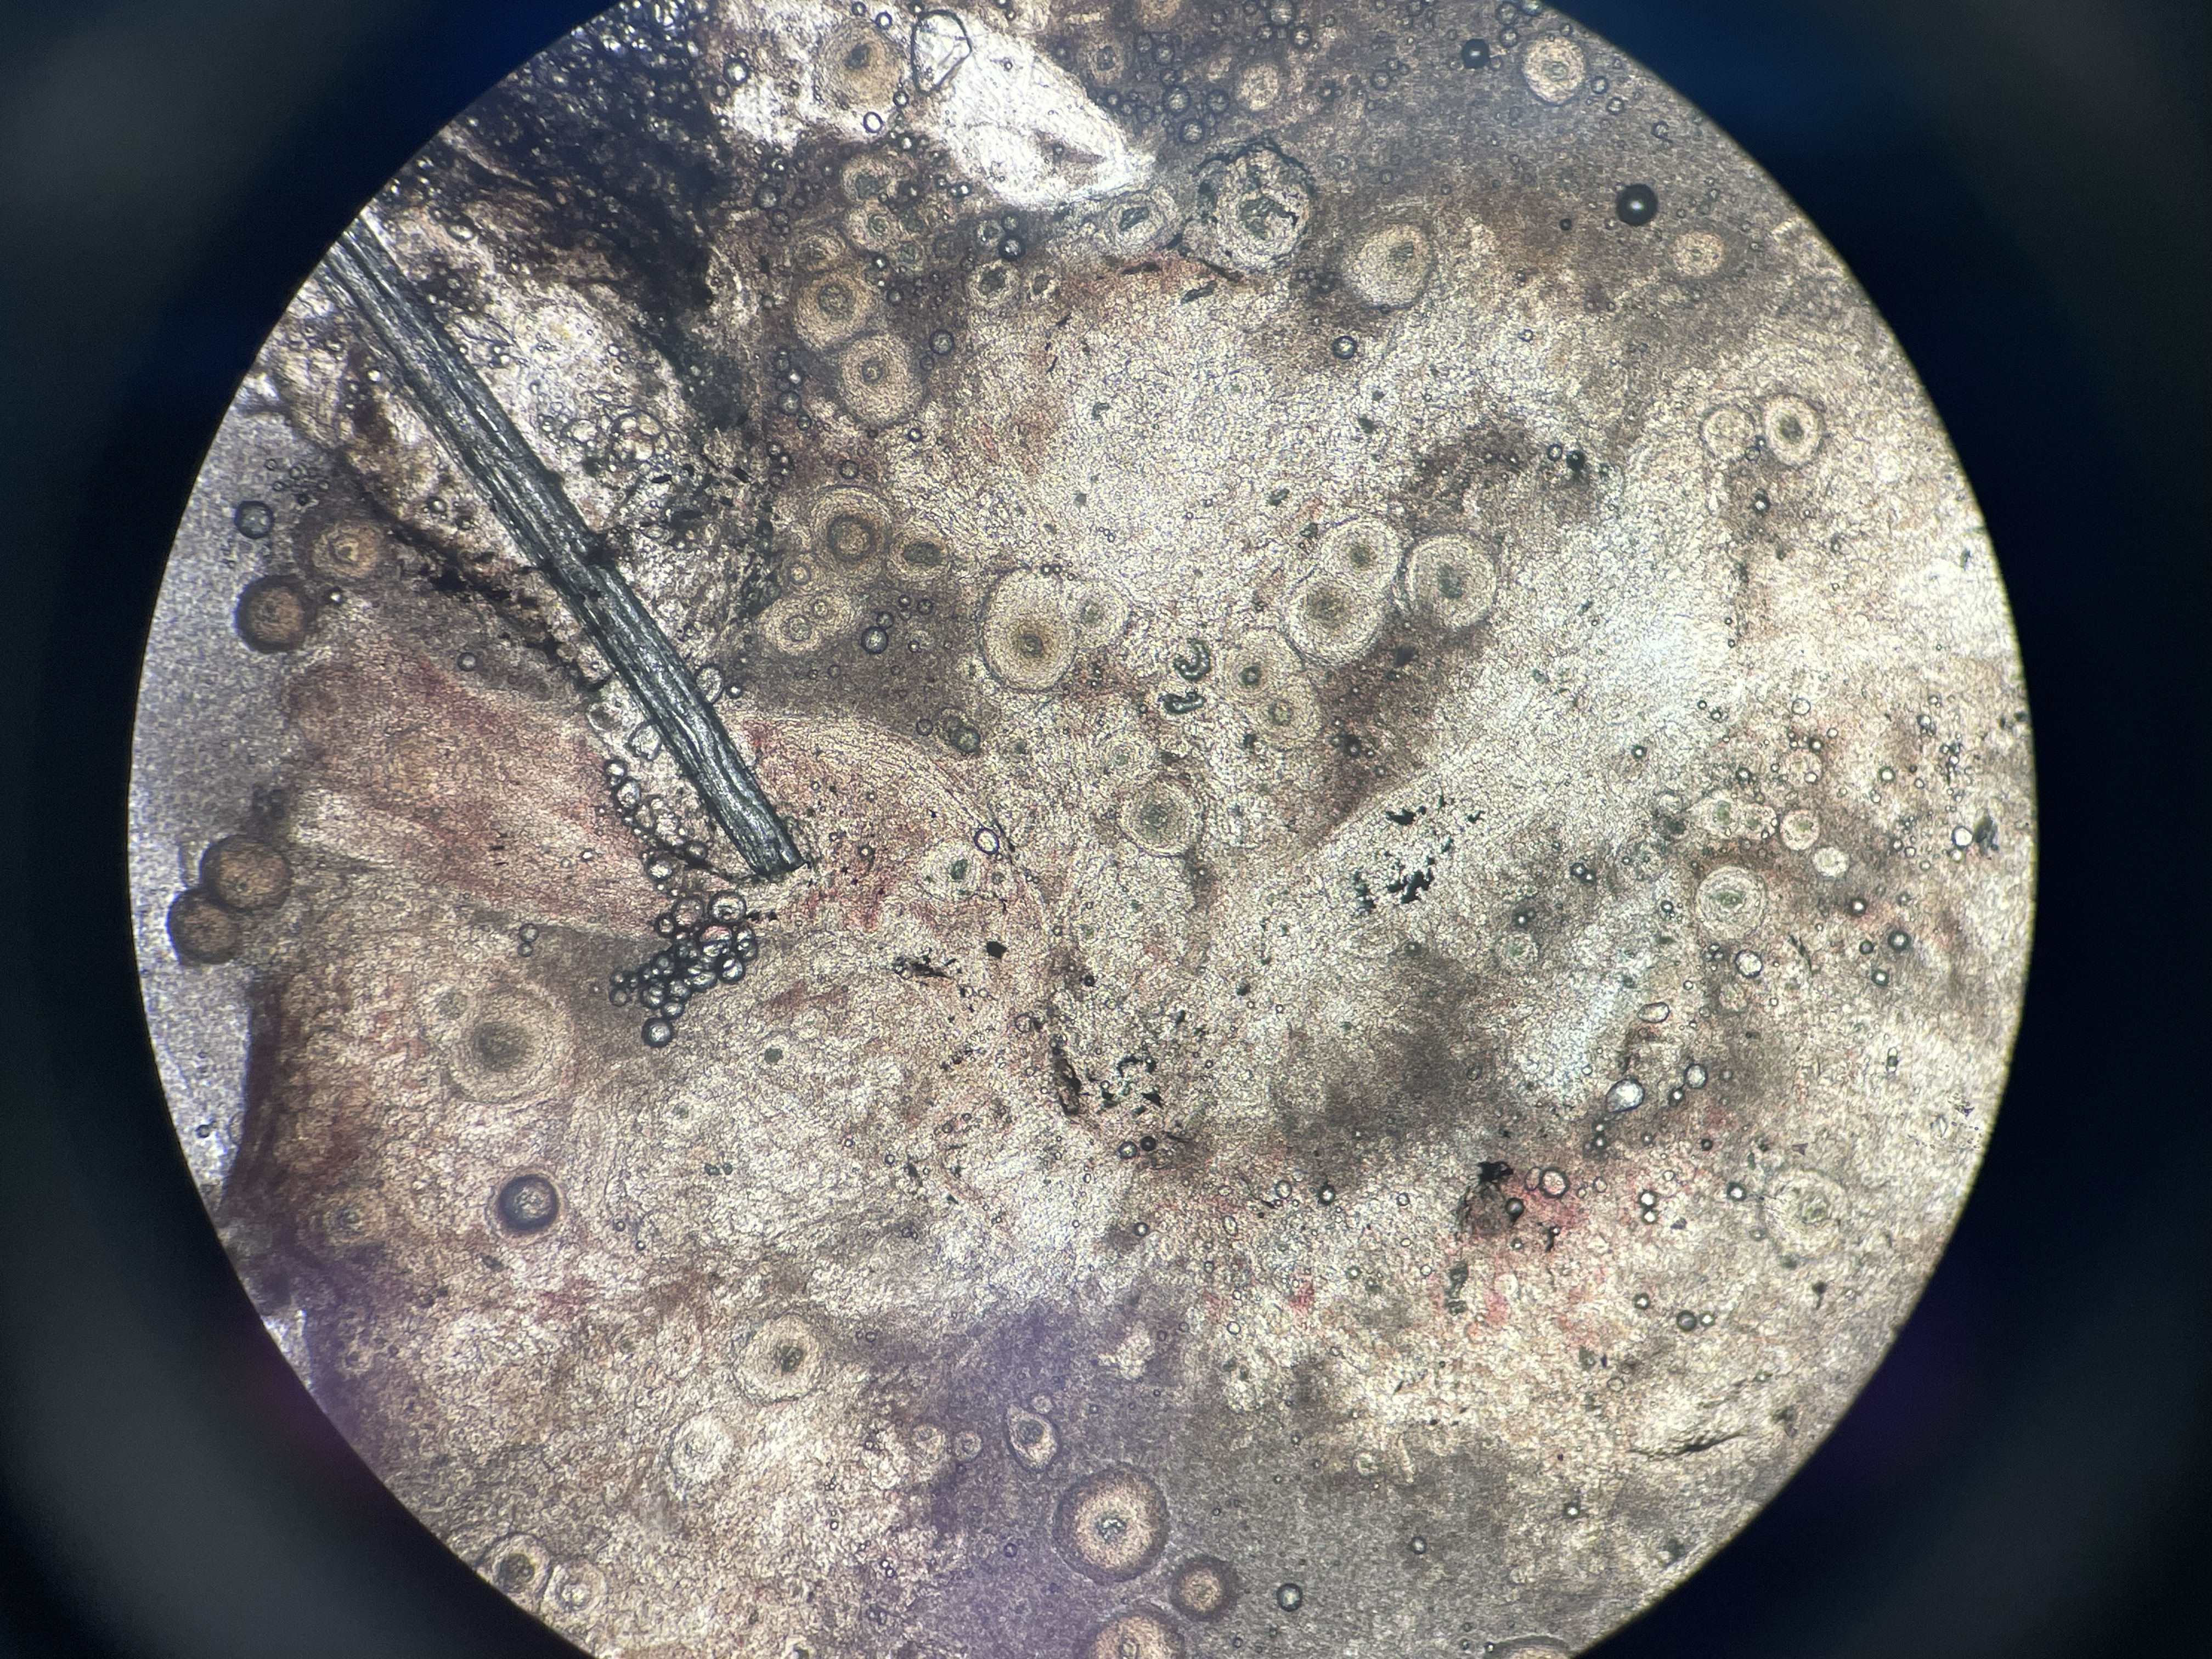

Systemic Granulomas

Agent: The cause is unknown. Some potential factors include infectious agents, metabolic issues, nutritional disorders, or autoimmune problems.

Symptoms: Common in meagre (Argyrosomus regius). Fish develop multifocal white nodules visible throughout the viscera, particularly in the kidney, which may become calcified over time. Microscopically, the nodules correspond to granulomas of concentric layers of epithelioid cells around a necrotic core.

Control: No treatment.